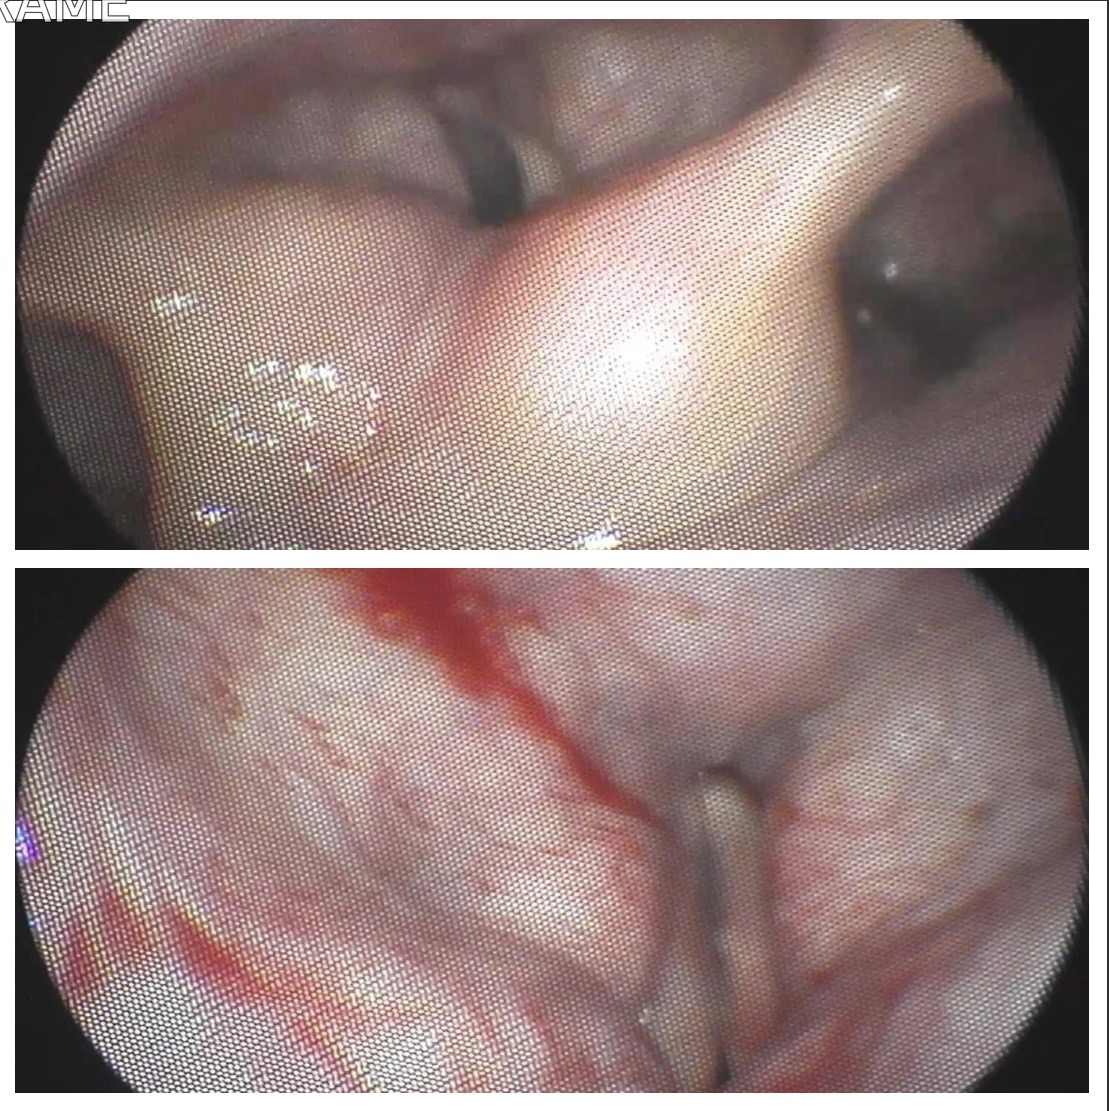

Caso: Lesión de cuerda vocal izquierda. Sospecha de carcinoma. Biopsia peroral.